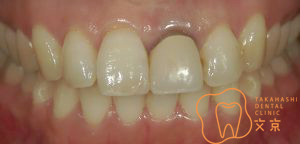

■前歯を治したい。 オールセラミックスによる審美治療

■前歯を治したい。40代男性 オールセラミックスによる審美治療

■前歯を治したい 精密審美治療・セラミックス治療

■前歯 精密審美治療

■前歯のセラミックス治療 審美治療

■前歯のオールセラミックス治療

■保険の前歯を直したい